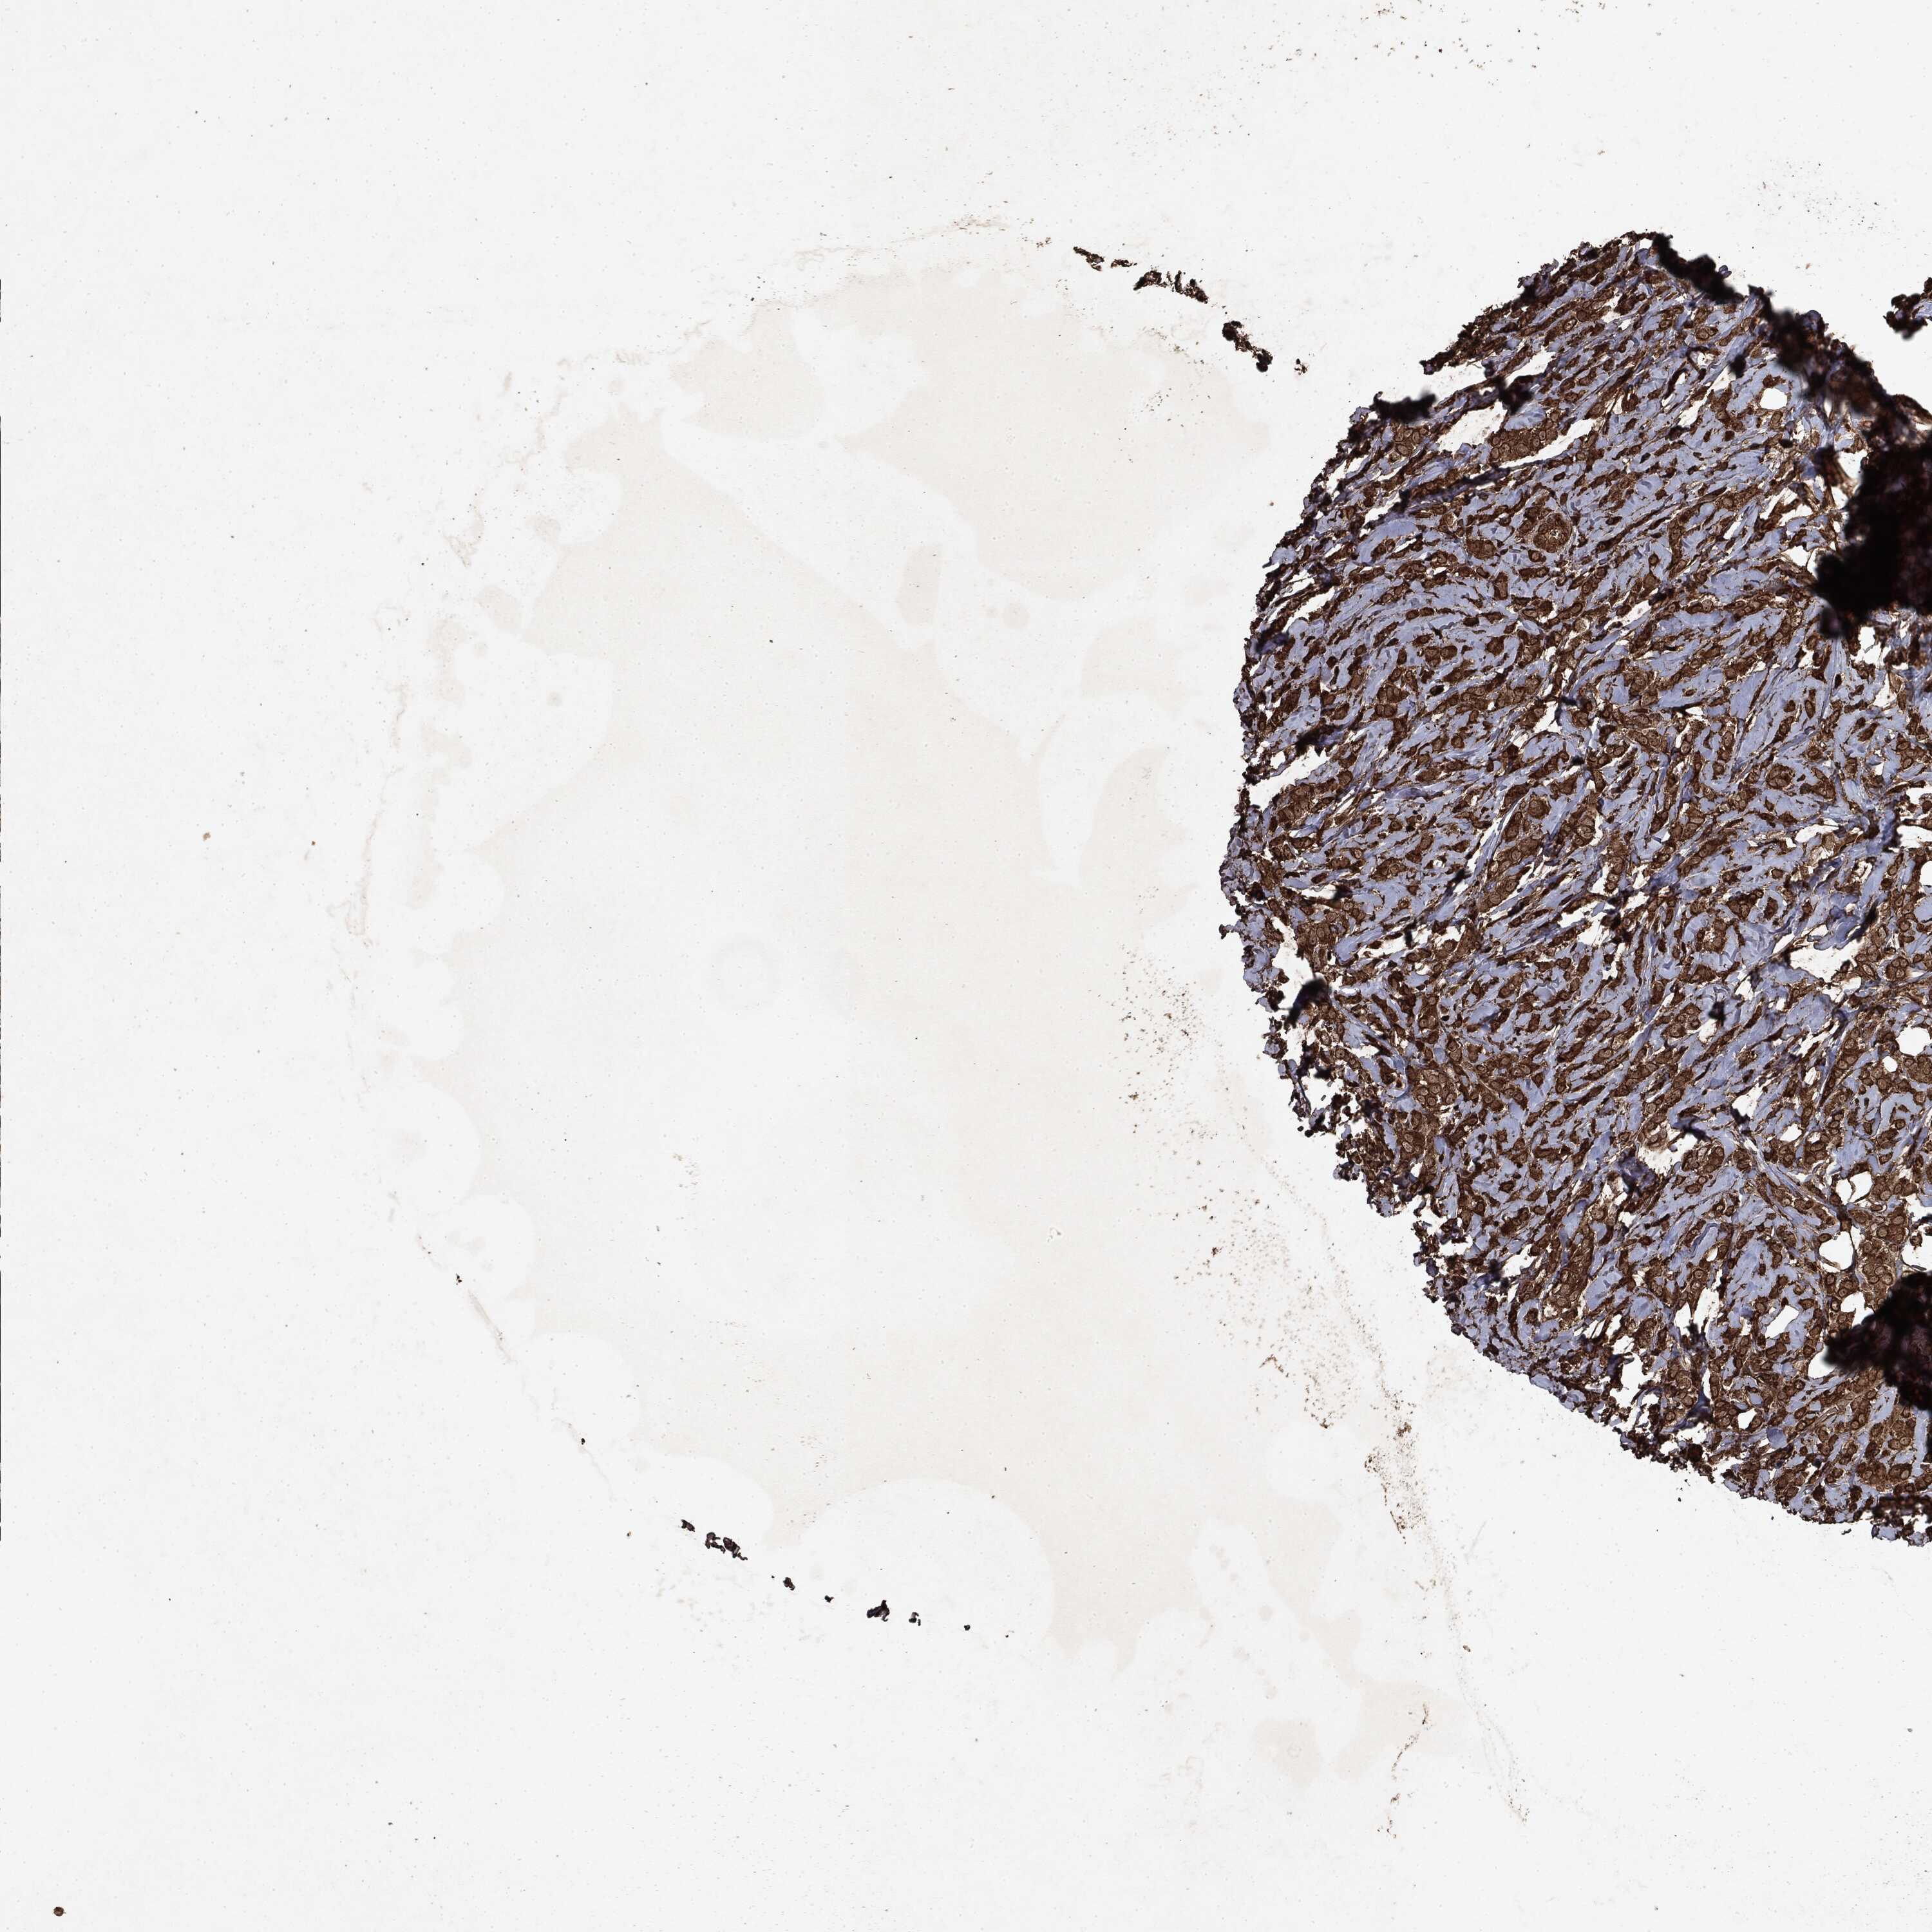

BRCA TCGA BRCA VALIDATION PROTEIN EXPRESSION

ANTIBODIES

AND

VALIDATION